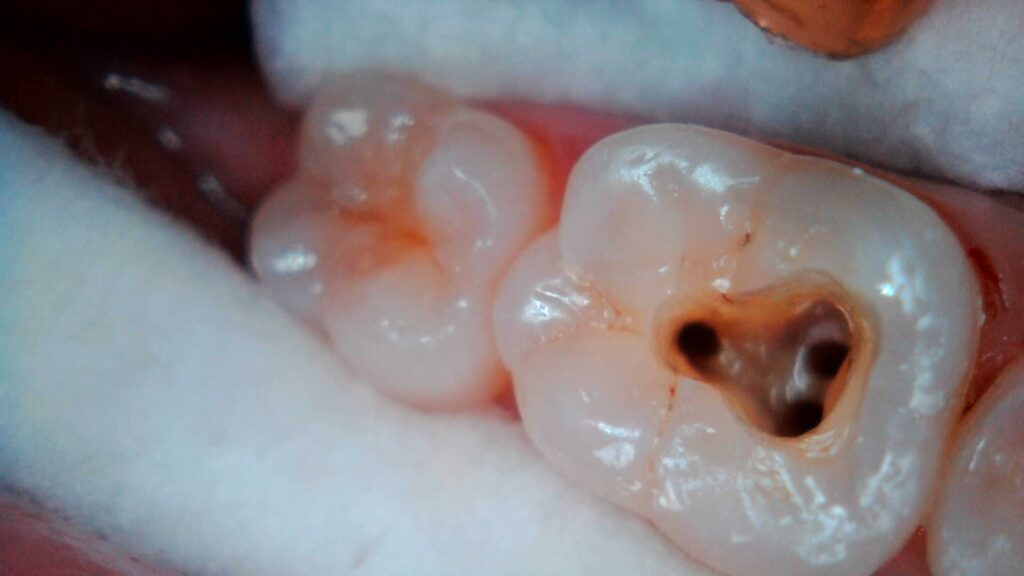

La Endodoncia es la rama de la odontología que se encarga del tratamiento de las patologías que afectan a los tejidos pulpares de los dientes como caries profundas, infecciones radiculares o fracturas.

Gracias a la endodoncia o tratamiento de conductos podemos conservar los dientes y su función. Cuando se deja que la caries dental evolucione o cuando el diente recibe un traumatismo importante éste termina afectando a los conductos donde está la pulpa dental (conocida como “nervio”). La acción de los microorganismos suele ser responsable de la infección e inflamación de la pulpa cuyo síntoma principal es el dolor agudo aunque a veces pueda pasar desapercibida. La evolución de esta inflamación termina en la “necrosis” o muerte de ésta, lo cual puede producir una infección o absceso a nivel óseo (flemón).

La Endodoncia limpia y conforma el interior de los conductos de las raíces dentales, sellándolos posteriormente impidiendo así la presencia de microorganismos en ellos. De este modo se consigue conservar el diente sin tener que extraerlo y la recuperación, en la mayoría de los casos, de la infección a nivel óseo.